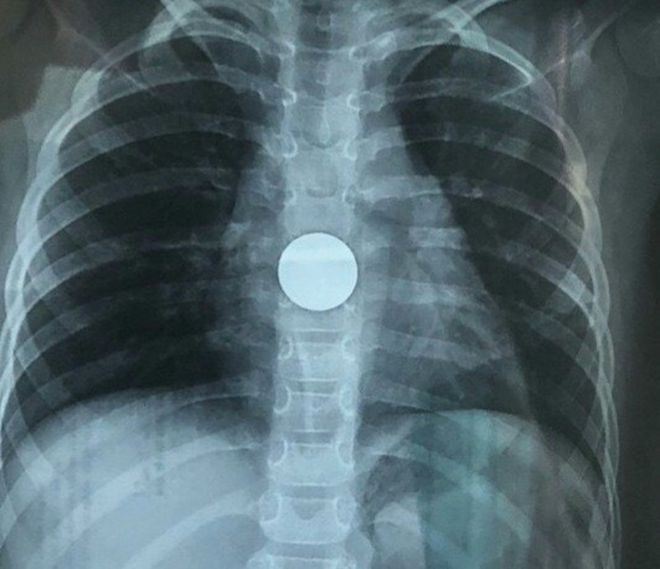

Đến khoảng 21 giờ cùng ngày, bé T. được chuyển đến Khoa Tai - Mũi - Họng, sau chụp X-quang, bác sĩ xác định dị vật là đồng xu, đang kẹt ở vị trí cách cung hàm trên khoảng 26 cm, rất gần với dạ dày.

| Chụp X-quang phát hiện đồng xu trong ổ bụng bé gái ẢNH: TRẦN THANH PHONG |